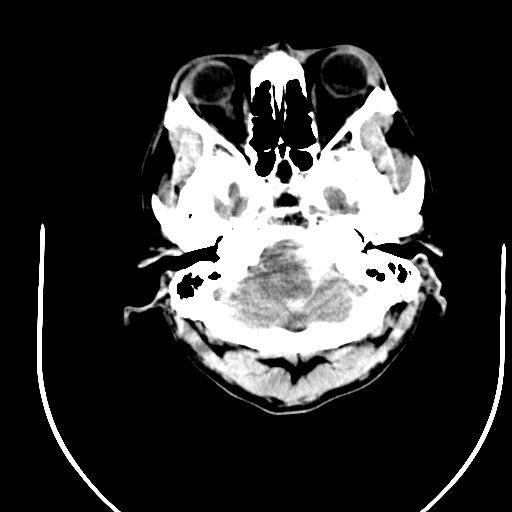

标题: CT24997:M,60Y,突发昏迷30分钟,有高血压病史。 [打印本页]

标题: CT24997:M,60Y,突发昏迷30分钟,有高血压病史。

1右侧基底节脑出血伴脑干出血并破入脑室系统脑疝形成2梗阻性脑积水

1)右侧基底节脑出血伴脑干出血并破入脑室系统。2)大脑镰下疝。3)梗阻性脑积水。